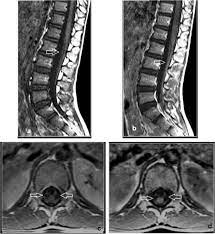

However, it can reveal nerve root enhancement and may be an effective diagnostic adjunct. The severity on mri does not correlate with severity of the clinical condition. Fisher syndrome, a clinical variant of guillain­ barre syndrome characterized by ataxia, are­ flexia, and ophthalmoplegia, brain stem lesions have been described with cranial mr.imaging (8). Its signs and symptoms are similar to those of other neurological disorders and may vary from person to person. Sagittal and axial post contrast t1 fs images shows smooth thickening and abnormal enhancement of the cauda equina and the ventral nerve roots. Moreover, gbs is also associated with any vaccination. Your doctor may then recommend: It is characterized by a triad of ophthalmoplegia, ataxia, and areflexia.

Clinical presentation is usually characterized by rapidly progressive, ascending, and symmetric paralysis of the extremities. Although no abnormalities were observed on brain and spinal magnetic resonance imaging and electroencephalography, peripheral nerve conduction velocity tests failed to evoke motor and sensory nerve action potentials. It is characterized by a triad of ophthalmoplegia, ataxia, and areflexia. Sagittal and axial post contrast t1 fs images shows smooth thickening and abnormal enhancement of the cauda equina and the ventral nerve roots. Scott olson / staff / getty images Moreover, gbs is also associated with any vaccination. Your doctor may then recommend: Mri is sensitive, but nonspecific, for diagnosis. The study findings are published in the journal neurological research. Mr imaging findings in eight patients (three male, five female; Immune checkpoint inhibitors (icis) have been increasingly used in the treatment of various types of tumors with favorable results. The most common result is a weakness and numbness that starts at the tips of the fingers and toes and spreads inward toward the body. Guillain barré syndrome (gbs) is characterized by demyelination and axonal degeneration of peripheral nerves.

Its signs and symptoms are similar to those of other neurological disorders and may vary from person to person. Sagittal and axial post contrast t1 fs images shows smooth thickening and abnormal enhancement of the cauda equina and the ventral nerve roots. Mri is sensitive, but nonspecific, for diagnosis. The diagnosis is usually established on the basis of symptoms and signs, aided by cerebrospinal fluid findings and electrophysiologic criteria. Clinical presentation is usually characterized by rapidly progressive, ascending, and symmetric paralysis of the extremities. Scott olson / staff / getty images Your doctor is likely to start with a medical history and thorough physical examination. It is the most common cause of rapidly progressive flaccid paralysis.

On csf analysis, the cell count is normal in 85% of patients, and high protein values are seen in 64%. Sagittal and axial post contrast t1 fs images shows smooth thickening and abnormal enhancement of the cauda equina and the ventral nerve roots. Clinical presentation is usually characterized by rapidly progressive, ascending, and symmetric paralysis of the extremities. Fisher syndrome, a clinical variant of guillain­ barre syndrome characterized by ataxia, are­ flexia, and ophthalmoplegia, brain stem lesions have been described with cranial mr.imaging (8). Typically, both sides of the body are involved, and the initial symptoms are changes in sensation or pain often in the back along with muscle weakness, beginning in the feet and hands, often spreading to the arms and upper body. Mr imaging findings in eight patients (three male, five female; With treatment, people may improve more quickly. However, it can reveal nerve root enhancement and may be an effective diagnostic adjunct. Your doctor may then recommend: The most common result is a weakness and numbness that starts at the tips of the fingers and toes and spreads inward toward the body. Moreover, gbs is also associated with any vaccination. Mri is sensitive, but nonspecific, for diagnosis. Immune checkpoint inhibitors (icis) have been increasingly used in the treatment of various types of tumors with favorable results.